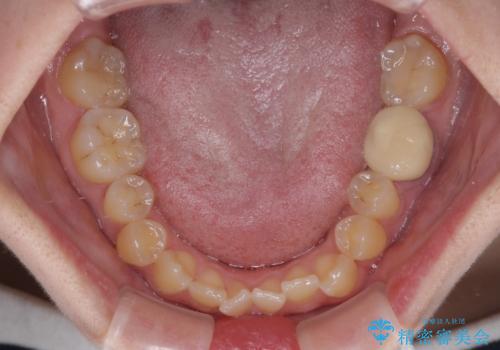

- 上顎の八重歯やデコボコを気にして来院された患者様です。

上顎歯列が狭窄していたため、急速拡大装置により上顎骨を側方に拡大しながら、ワイヤー装置にて矯正治療を行うこととしました。